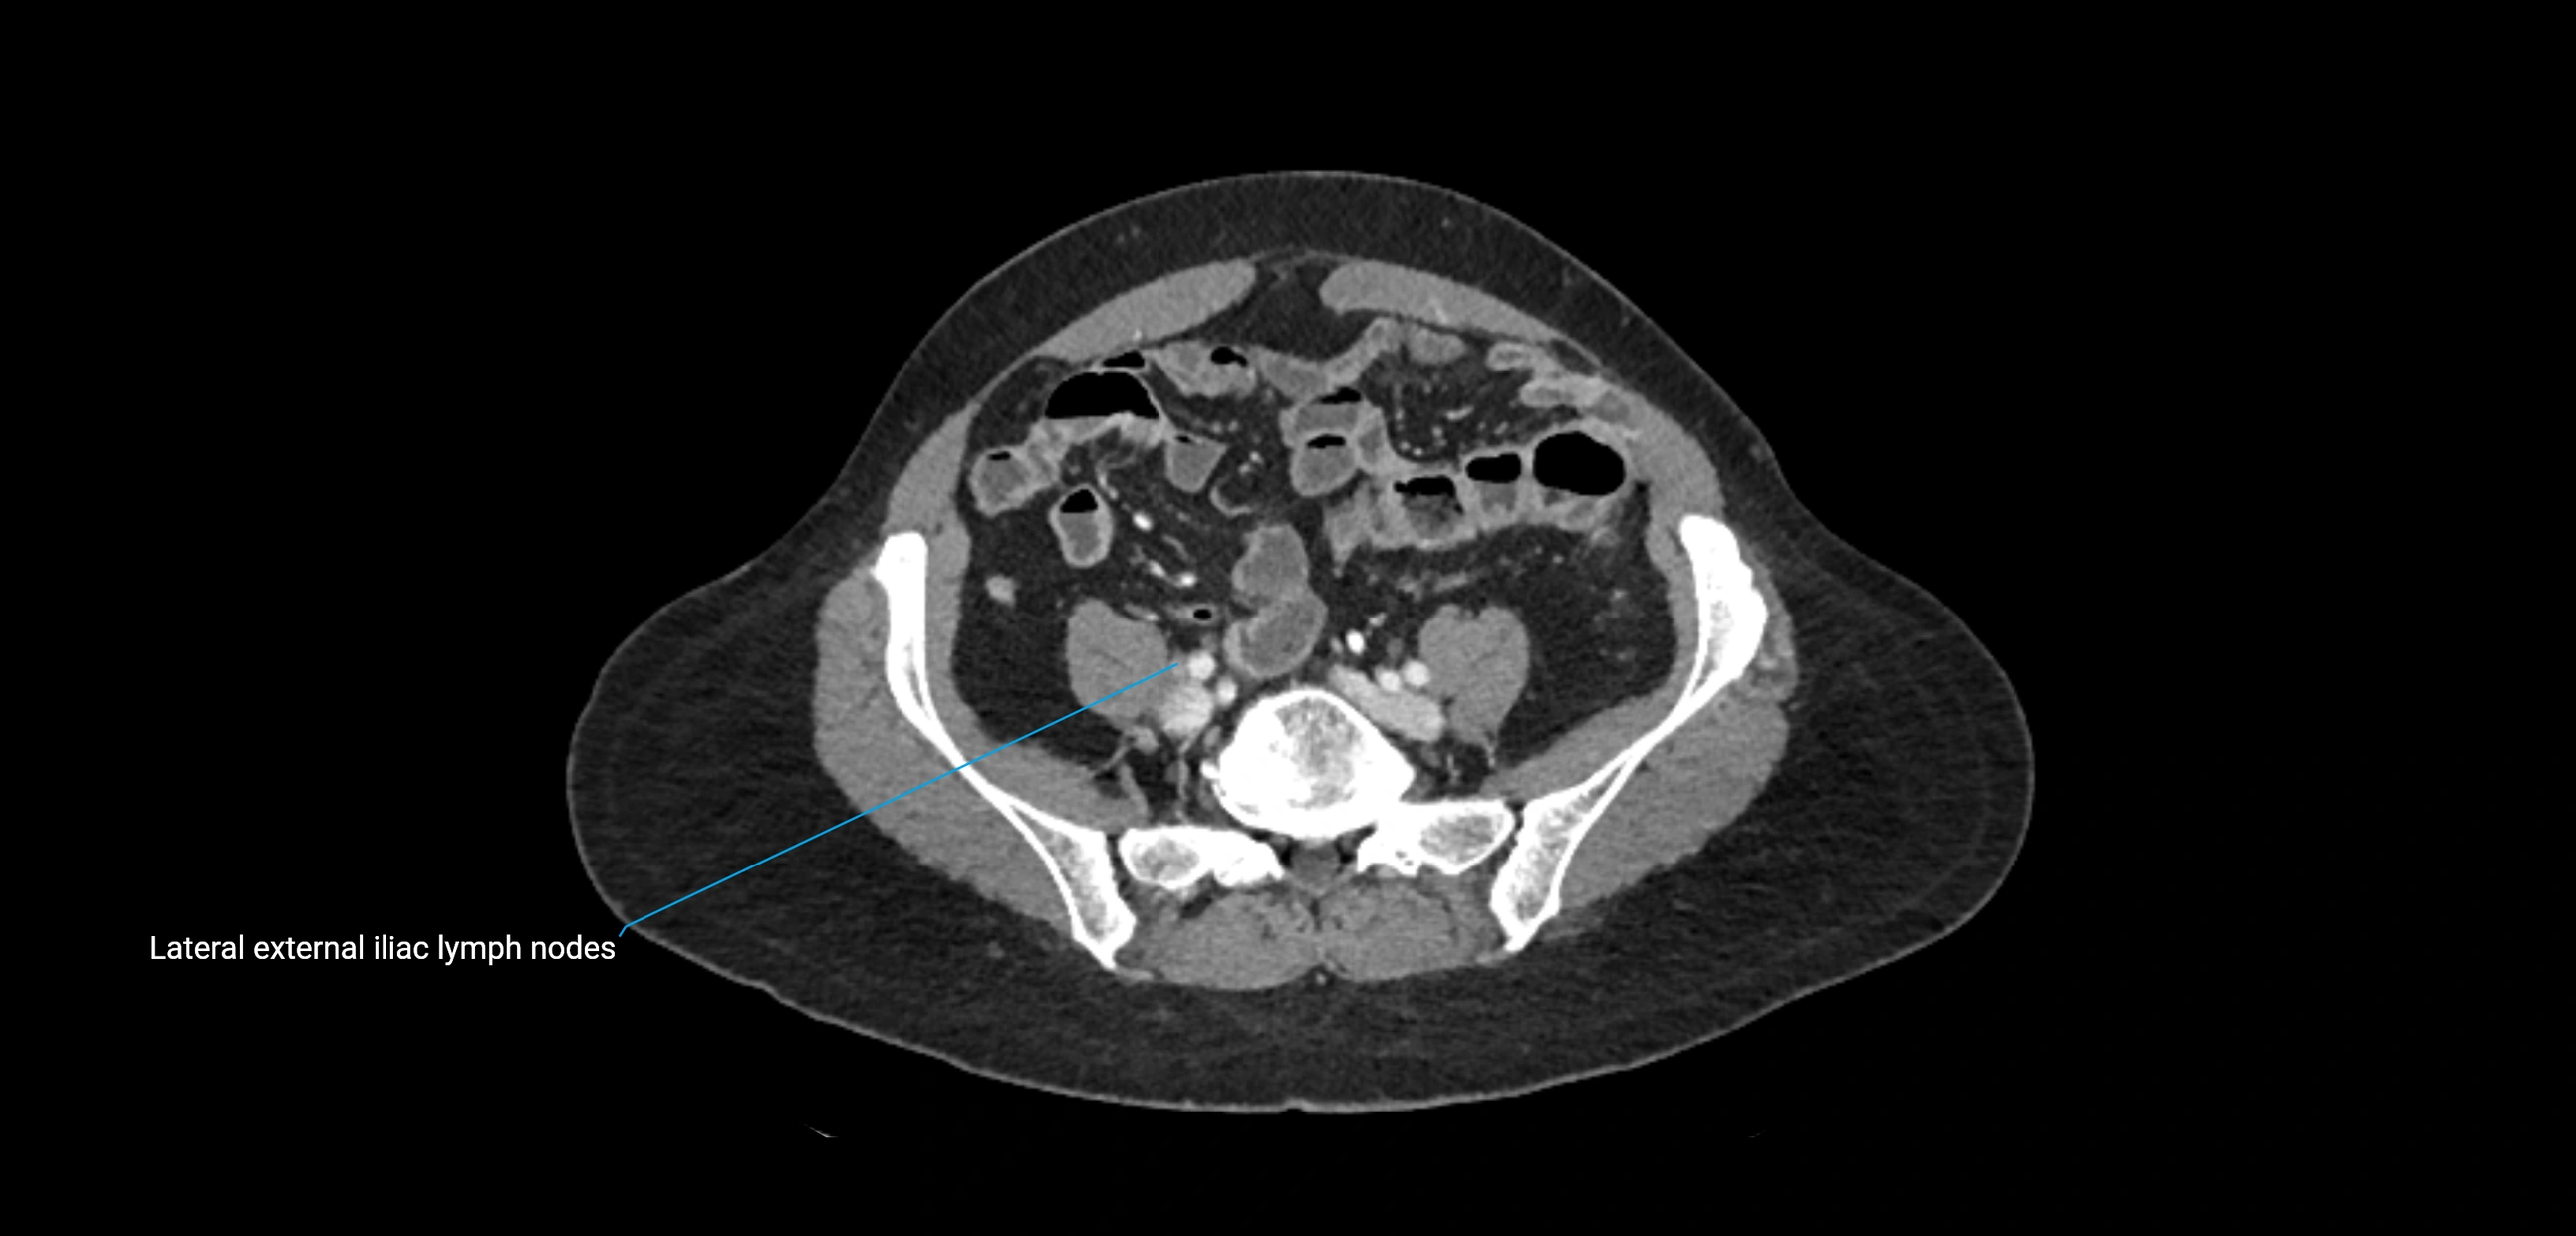

CT Appearance

CT Post-Contrast:

• Normal nodes enhance homogeneously

• Malignant nodes may show heterogeneous enhancement, central necrosis, or conglomerate formation

• Size >1 cm short axis is suspicious, though morphology and distribution are equally important

CT Venography (CTV):

• Demonstrates nodal encasement or compression of adjacent vessels (aorta, IVC, renal veins)

• Useful in staging testicular and ovarian malignancies

• Provides 3D reconstructions for retroperitoneal lymph node dissection planning